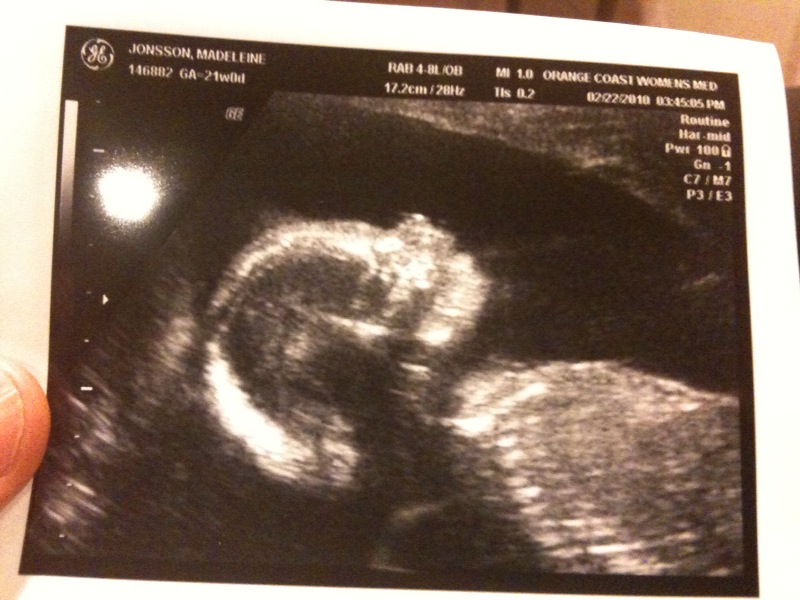

Nope, det hade inte växt ut en snopp sen vårt förra UL och det är fortfarande

en tjej 🙂 Tihi så spännande me en lillasyster. Jag säger hela tiden att hon ska

nåt annat. Allt såg iaf bra ut. Alla mått va fina. Njurar, mage, blåsa, huvud,

läppar, näsa, hjärta.etc 😀 Fick en massa fina bilder med oss hem.

Enligt UL:et är jag gången 5 dagar längre än förra UL:et visade.. så BF

skulle vara 5 Juli istf 10. Men jag är ändå inställd på 10:e. Kommer nog